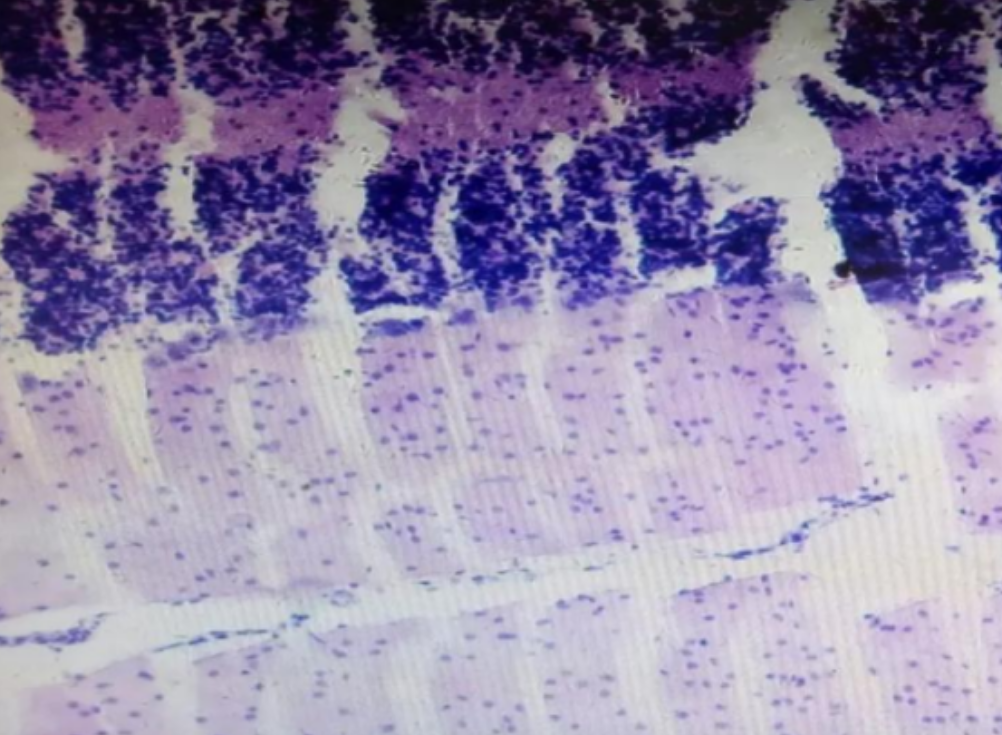

形成原因:切片经梯度乙醇处理后没有完全脱水,导致二甲苯透明、中性树胶封固后残留大量水分。 解决方法:首先移去盖玻片,用二甲苯溶解封固剂如中性树胶,再将切片置入无水乙醇内,待切片重新脱水完全后,用二甲苯透明处理,中性树胶封固。要注意所有用于脱水和透明的液体,在使用一定时间后,应及时更换。 二、细胞核呈红、棕色 形成原因:苏木精染色液过度氧化,切片在苏木精染液染色后返蓝不足。 解决方法:每次染色之前检查苏木精染色液的染色能力,发现苏木精染色液氧化过度应及时更换。此外,切片经苏木精染色后,要给切片以足够的蓝化时间,蓝化过程可用流水、温水、弱碱性溶液(如稀氨水或0.2%碳酸氢钠)等处理。 三、切片在脱蜡后出现大片白色斑点 形成原因:由于烤(烘)片温度太低,切片上的组织蜡膜在脱蜡前没有充分烤(烘)融化。或是因为切片在二甲苯液中停留时间不足,或二甲苯使用过久,造成的脱蜡不彻底。 解决方法:若是由于切片烤(烘)温度低所致,可以先用二甲苯去除切片上的封固胶,然后重新用二甲苯脱去切片上的石蜡,再进行后续染色。若是由于切片在脱蜡的二甲苯中停留时间不足或脱蜡二甲苯使用过久浓度不足所致,则需将切片退回到二甲苯中,停留较长时间,或更换二甲苯液体重新脱蜡,再入乙醇重新脱二甲苯,入0.5%盐酸水溶液褪色后,重新HE染色。 四、细胞核苍白暗淡,即苏木精染色太淡 形成原因:切片在苏木精染色液停留时间太短;苏木精染色液过度氧化,失去染色能力,不能再继续使用;分化步骤处理时间过长;固定不及时。此外值得注意的是,若骨组织细胞核暗淡,大多是脱钙过度造成的。 解决方法:切片重新染色。如果组织在酸性固定液(如Zenker、Bouin)或非中性缓冲甲醛液固定时间过长,细胞核染色能力将减弱,需增加其在苏木精染色液的时间,或用一些方法增加组织的嗜碱性,以改善细胞核的着色。例如,上述组织玻片可以使用Weigert铁苏木精染色液。如果组织是用Zenker液固定的,可将切片脱蜡后放在5%碳酸氢钠溶液3~4h,流水冲洗5min后染色。如果组织是用Bouin液固定的,可将切片脱蜡后放在5%碳酸锂1h,流水冲洗10min后染色。 五、细胞核过染,苏木精染液占据了细胞质 形成原因:玻片在苏木精染色液停留时间过长,或是切片太厚、分化步骤时间太短。 解决方法:如果不是因为切片太厚(用显微镜仔细上下微调,只有一二层细胞核层次),就需将切片进行脱色、漂白、重新染色,适当调整染色和分化时间。但如果确定是由于切片太厚导致的细胞核过染,则需要重新切片。 六、伊红着色淡 形成原因:可能是伊红染液pH值大于5,也可能是蓝化液残留过多,切片太薄,或是切片经伊红染色后在乙醇脱水时间过长。 解决方法:检查伊红染液pH值,必要的话,用乙酸将其调节在4.6~5.0之间,从而使伊红染色色彩艳丽。此外,确保每次蓝化步骤完成后,使用的弱碱性溶液被充分洗去,玻片上没有残留的弱碱性溶液。最后,检查切片的厚度,且脱水时不要让切片在低浓度乙醇中停留时间过长,因为含水多的低浓度乙醇会将切片伊红的颜色分化掉。 七、细胞质过染、分色不足 形成原因:伊红染色液浓度太高,特别是存在焰红燃料、四溴四氯荧光素钠。切片在伊红染色时间过长,或是切片在伊红染色后经乙醇脱水步骤时时间太短,而使乙醇分化伊红的作用不能产生,都能够使细胞质过染。 解决方法:适当稀释伊红染色液,减少伊红染色时间,或使切片在乙醇脱水等步骤时,停留时间相对均匀。同样,也要检查切片的厚度是否合适。 八、切片中出现蓝黑色沉淀物 形成原因:苏木精染色液中的金属膜黏附在玻片上。 解决方法:染色前仔细过滤苏木精染色液,建议使用半氧化苏木精染色液,如Gill苏木精染色液,可以避免过多的金属膜产生。 九、光镜下切片某些区域难以聚焦 形成原因:盖玻片上可能有封固切片的封固剂。 解决方法:移去盖玻片,重新用干净的盖玻片封片。检查切片封片方法,是人工手工封法,还是机器自动封法,如有问题及时调整。 十、封固剂从盖玻片与载玻片之间的缝隙回缩 形成原因:盖玻片弯曲或不平整,或是封固剂含二甲苯过多,稀释过度。 解决方法:移去盖玻片,重新找一张盖玻片,用干净的封固剂封片。如用手工封片法,保证在封固结束时,封固剂容器盖子为紧闭状态。且尽量使用小的容器盛装封固剂,一旦封固剂太黏稠,就可以选择废弃。 十一、细胞核呈灰蓝状态 形成原因:可能由于组织处理温度过高、过热,在液体石蜡中停留的时间过长。或是固定时间太短后,直接在高浓度的乙醇中进行了脱水处理。 解决方法:理论上来说,仅在组织浸蜡步骤才进行加热,组织不能在热蜡液中停留太久。如果由于某些原因不能进行下一步包埋处理,可将组织连同塑料包埋盒一并放置在室温空气中,冷却凝固,以备包埋。待需要包埋时再重新加温直至石蜡融化即可。组织在处理前必须确保固定良好,脱水最好能从低浓度的乙醇开始。 十二、类色素的点状结晶和黑色光滑细胞核 形成原因:这种裸核改变是因为切片封片前放置在空气中的时间太长,以至于二甲苯挥发,切片干燥。 解决方法:移去组织切片上的盖玻片和封固剂,重新处理。将切片水洗数分钟,然后重新脱水、透明、封固。封片过程中要保持组织切片的轻度湿润,尽量不要让其干燥。 十三、染色过淡或过浓 解决方法:如果染色过淡,可以增加染色剂的浓度、延长染色时间或更换新鲜的染色剂;如果染色过浓,则应减少染色剂的浓度或缩短染色时间。 十四、切片出现叠加褶皱 形成原因:新购买的玻片洁净度不够、用镊子撑开切片时操作不够熟练未能平整伸展,或玻片表面有油脂,切片粘贴不牢。另外,烤片时间不足、烤片温度过低或切片过厚造成切片脱落,都会造成重叠或有皱褶的情况。 解决方法:新购买的玻片最好能用硫酸清洁液浸泡一晚,然后流水冲洗干净。在适宜的温度下烤片时间宁长勿短,保证有充足的烤片时间和温度。另外,切片刀要锋利,才能切出厚薄适宜的切片,保证切片不会因为过厚而脱落。 十五、组织残缺不全或有刮划痕迹 形成原因:组织残缺不全是由于切片时修整蜡块时深度不够、组织没有全部暴露于切面。切片的刮划痕迹是由于切片刀的刀锋有缺口、包埋的组织有异物,或是钙化组织、骨组织及包埋石蜡有沙粒造成的。 解决方法:修整蜡块时保证组织块全部暴露于切面,切片时保证切片刀的锋利没刀口。同时在组织取材时去除手术异物和钙化组织。最后,骨组织要完全脱钙,这样可以保证切片的完整和平整美观。 *注:由于实验中导致结果出现误差的原因多种多样,以上内容仅供参考,具体根据实际情况进行判断。